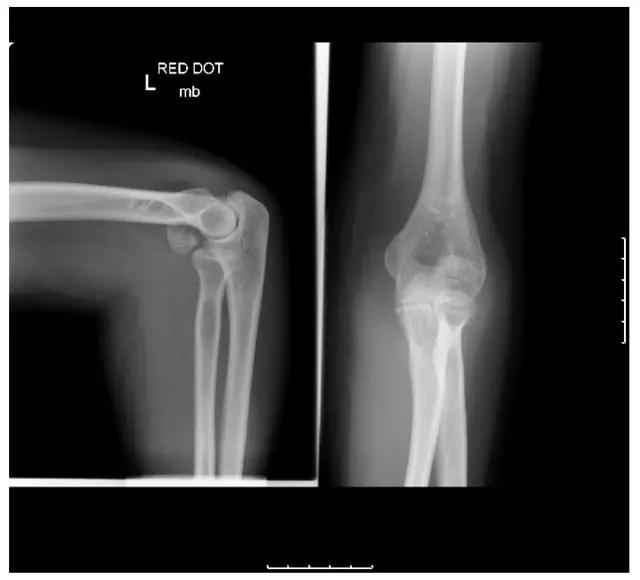

5. Kocher-Lorenz 骨折

单纯肱骨小头骨折。

Kocher-Lorenz 骨折(来源:The often-missed Kocher-Lorenz elbow fracture. Revue de Chirurgie Orthopédique et Traumatologique, Volume 95, Issue 7, November 2009, Pages 658-661)

6. Hahn-steinthal 骨折

全肱骨小头骨折,为一种少见的关节内骨折,多见于成年人。常由于跌倒时手过度伸直或在屈肘时因桡骨小头撞击肱骨小头,并同时有外翻力存在时发病,亦可伴有滑车骨折与内侧副韧带的撕裂。X 线表现为全肱骨头骨折,向上移位。

Hahn-steinthal 骨折 X 片(来源:Hahn-Steinthal fracture: a case report.BioMed central Cases Journal20081:239)

Hahn-steinthal 骨折 CT 片(来源:Hahn-Steinthal fracture: a case report.BioMed central Cases Journal20081:239)